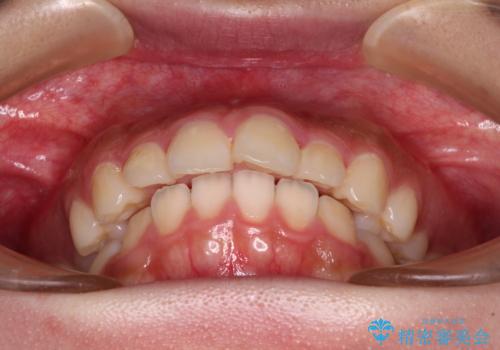

- 飛び出した上顎前歯と、閉じにくい唇、口元の突出した印象の横顔を気にして来院された患者様です。

事前の予想通り、長期間を要する治療となりましたが、横顔の印象が劇的に変化し、患者様には大変満足していただきました。